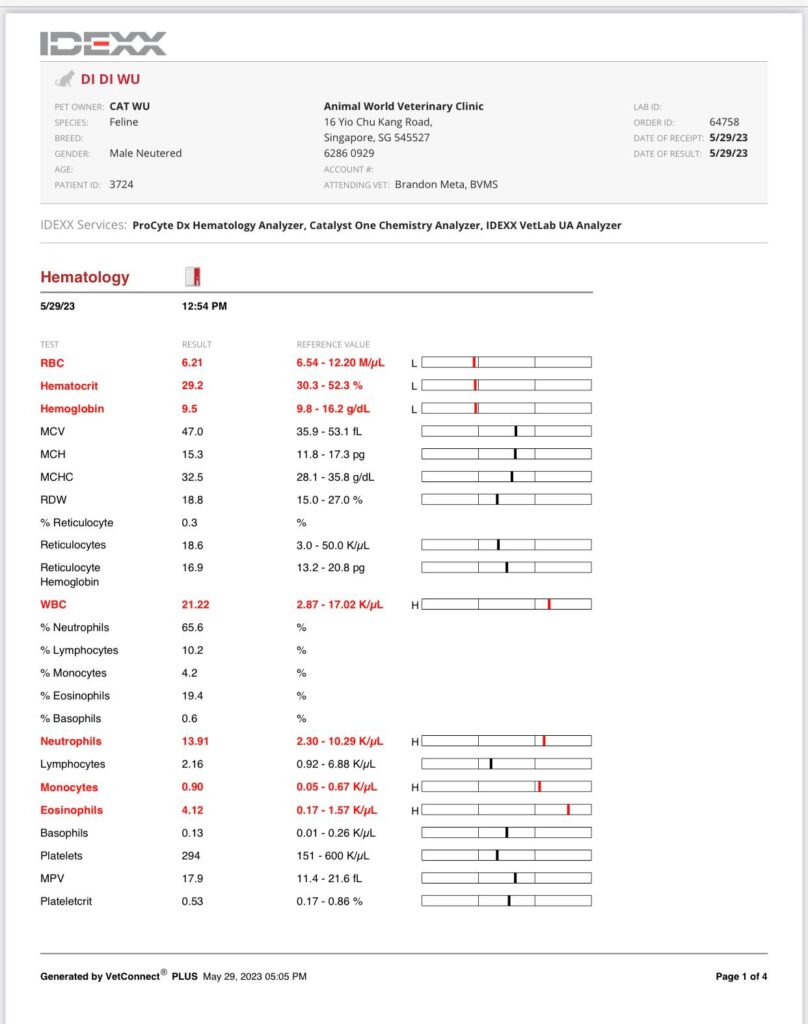

12.10pm: seen dr Brandon.

4.26-8kg, weight unchanged.

Keep sneezing. W blood also. The wall also the carrier bag also. Can’t feel anything from the teeth side, cos both blood from both nostrils. So even take head X-ray can’t see the back from the nose, just whack Clav 10 days 0.25ml. See first.

Cbc Chem10 done. His blood is soooo dark red. yet 29% only!?

HCT 29.2% – monitor le. Alt 216. Think ornipural working ok for him – continue, dr Brandon says that’s what he use last time like a supplement so no harm giving.

Urine taken by cysto, didi not ok w bladder expression.

GGT and UPC back to normal. He say ok for me to stop both urosofalk and semintra (ha I know dr d would say no). recheck 2-4 weeks after stopping. I’ll book review 3 weeks later.

Night: given him Clav 0.25ml and ornipiral. No more oral med.